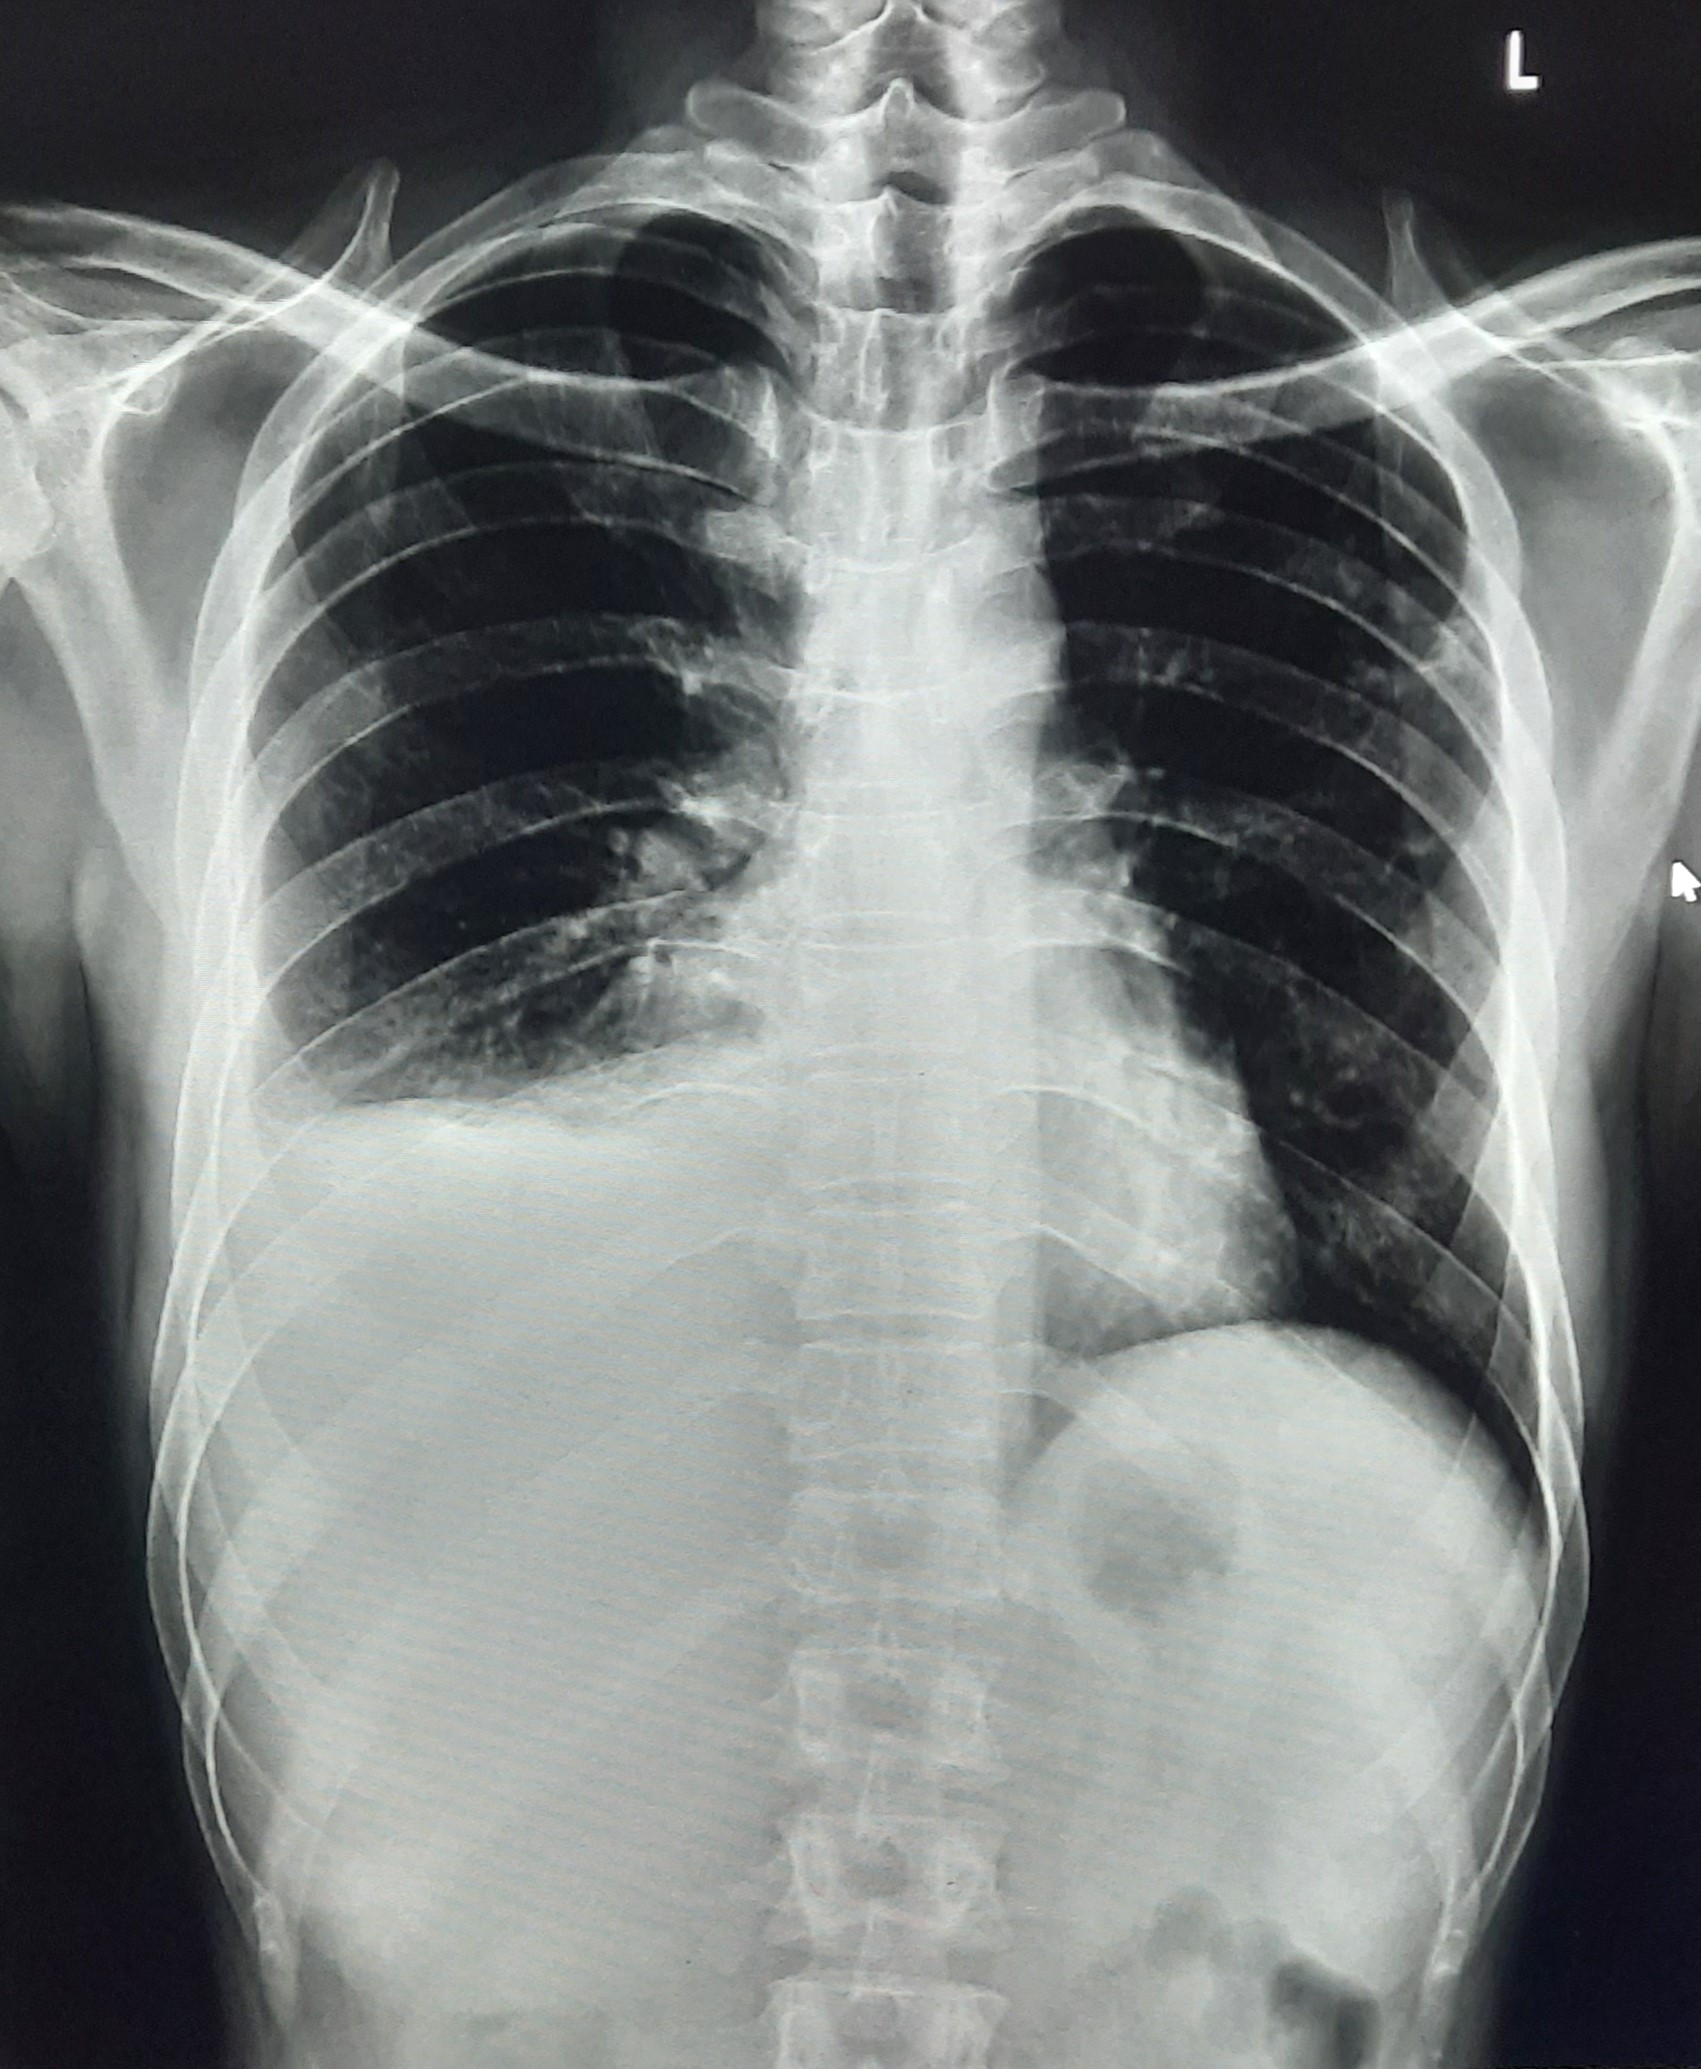

| 127 | IGGMC, Nagpur, Nagpur | P2 | 29-4345 | Hiraman Tembhurne | Consent taken on Paper | 62 Yrs. |

Provisional Diag : Dyspnea

Final Diag : Post TB With Interstitial Lung Disease |

Post TB Sequelae | Bilateral Cystic Opacity Upper, Mid & Lower Zone/ Bilateral Reticular Opacites/ Bilateral Fibrotic Bands Present/ Decrease Lung Volume/ Few Old Calcific Nodules | Abnormality visible on x-ray |